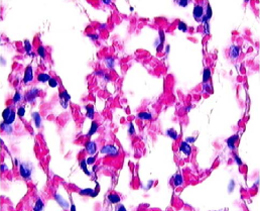

Figure 4. Oleic Acid Furue et al.Note: mild intra-alveolar infiltrates, intra-alveolar deposition of protein and intravascular protein. Also note that the alveolar walls remain thin. |

Figure 4. Oleic Acid Furue et al.